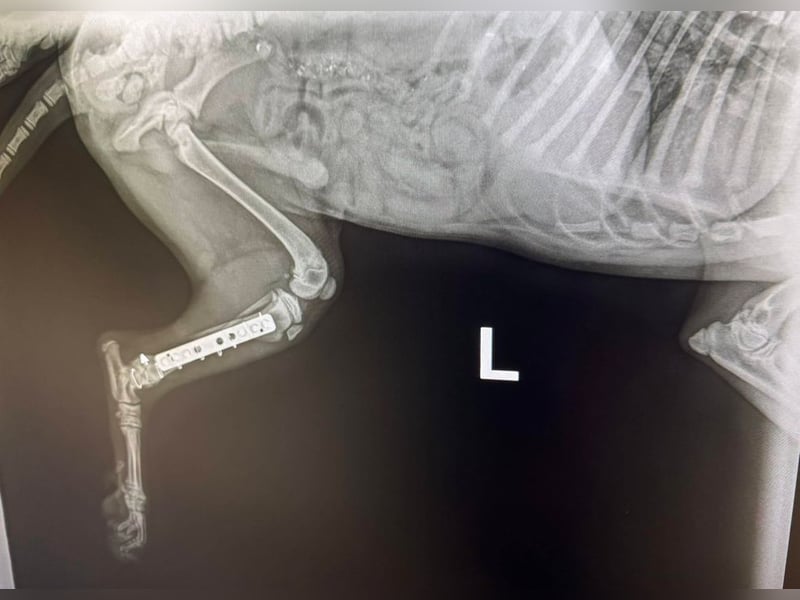

Bemerkungen: Hubsi wurde von einem Auto angefahren. Er hatte ein gebrochenes Hinterbenchen. Dieses wurde erfolgreich operiert.

Hubsi ist ein sehr lebhafter und verspielter Welpe und seit Mitte März 2026 in unserem Partnertierheim. Er kam zu diesem Zeitpunkt direkt aus der Tierklinik, denn er wurde in der Nähe einer Romasledlung von einem Auto angefahren und erlitt einen Bruch des Hinterbeinchens. Er wurde natürlich operiert und erholt sich momentan bei der Tierheimleitung im Wohnhaus.